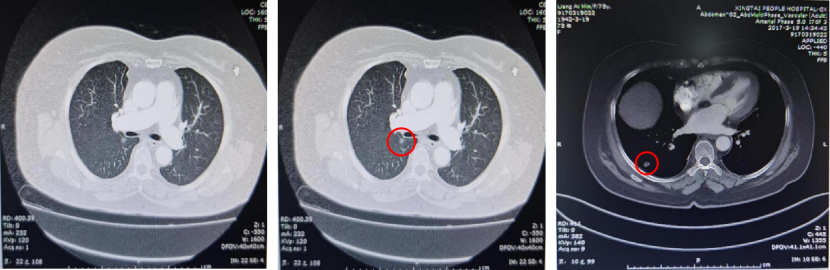

基本信息:性别 女,年龄 78岁,身高 159cm,体重 62kg。 主诉:结肠癌及肝转移瘤术后2年6个月(首次就诊时间为2018-09-10)。 既往史、个人史:“2型糖尿病”20年,予“二甲双胍 0.5g 口服 2次/日、门冬胰岛素注射液皮下注射,早 30U,晚 28U;甘精胰岛素皮下注射 20U ”降糖治疗,血糖控制一般。 家族史:无特殊。 02 初诊病史 体格检查、B超、CT及其他辅助检查。 体表面积1.60m,体格检查:浅表淋巴结未及肿大,双肺呼吸音粗,未闻及干湿性啰音,心律规整,未闻及杂音,腹壁可见陈旧性手术瘢痕,愈合良好,腹软,未及肿物,无压痛,肛查-,双下肢无水肿,起病隐匿,体检行腹部超声发现肝脏占位。 肠镜(2016-3-12):乙状结肠肿物。 咬检病理:(乙状结肠)腺癌。 肝胆胰增强CT(2016-3-10):肝左叶占位。 考虑:乙状结肠癌Ⅳ期 肝转移。 2016-3-21 于外院行“乙状结肠癌根治术+肝左叶转移瘤切除术”,术中予输血治疗,术后恢复慢,切口延期愈合。 术后病理:结肠中分化腺癌伴坏死形成,大者3.5cm×3.2cm×0.5cm,癌组织侵及浆膜脂肪层,脉管内癌栓形成,小者1cm×1cm×0.5cm,癌组织侵及粘膜下层。肠壁周围淋巴结癌转移(3/6),T3N1M1。(肝左叶)肝脏转移性腺癌伴大片坏死形成,大小6.6cm×6cm×4.5cm,结肠来源,残端及吻合口上下缘肠壁未见肿瘤侵及。 基因检测:KRAS、NRAS、BRAF 均未见突变。 初步诊断:乙状结肠癌Ⅳ期(pT3N1M1),同时性肝转移,中分化腺癌,2型糖尿病。 03 治疗方案 2016-4 XELOX 方案化疗1周期(具体剂量不详)因不良反应较重,未完成术后辅助治疗疗程。未予后续治疗,定期复查,病情稳定 胸腹CT(2017-3-19 ):右肺下叶新结节,考虑转移;肝左外叶转移瘤切除术后改变。 2017-4-1 于外院行局部肺肿物射频消融术,无治疗反应,恢复良好。 胸CT(2017-12-5):肺部新发结节,考虑转移。 【一线治疗方案(2017-12至2018-9)】 卡培他滨 1.5g po d1-14 q3w,共10个周期。 不良反应:1度消化道反应。 期间疗效评价:SD。 胸腹增强CT(2018-9-11):符合结肠癌切除术后,肝左叶切除后改变,双肺多发结节,部分较前增大。 2017-12-5 2018-9-11 建议调整方案治疗,患者家属拒绝,继续口服卡培他滨至2019年3月。 疗效评估: ECOG PS评分1分,新发活动后胸闷、气短症状 胸腹平扫CT(2019-3-26):双肺多发结节,较前增大;肝左外叶转移瘤切除术后改变。 2018-9-11 2019-3-26 评估PD。 【二线治疗方案(2019-4至2020-5)】 贝伐珠单抗 300mg ivgtt d0(体重62kg); 卡培他滨 1.5g po d1-14 q3w,共15周期。 不良反应:1级高血压、1度消化道反应。 疗效评估: 胸腹CT(2020-5-21):符合结肠癌术后、肝左叶切除术后,肝左切缘旁异常密度灶,左髂总动脉旁淋巴结;双肺多发结节,部分较前增大,右肺门肿物较前增大。 疗效评价:PD。 【三线治疗方案(2020-5至2020-10)】 西妥昔单抗 600mg ivgtt d0(体表面积1.66 m2); 亚叶酸钙 500mg ivgtt d1; 氟尿嘧啶 500mg ivgtt ,随后3500mg iv泵入 q2w,共9周期。 不良反应:无皮疹、腹泻、恶心、呕吐等。 疗效评估: 胸腹平扫CT(2020-09-07):右肺下叶背段软组织肿块,较前略减小,双肺多发小结节,转移瘤,同前;结肠癌术后、肝左叶切除术后改变,肝左切缘旁异常密度灶同前相仿,腹膜后左侧髂总动脉旁淋巴结同前。 2020-7-23 2020-9-7 疗效评价:SD(缩小趋势)。 胸腹平扫CT(2020-10-24):右肺下叶背段软组织肿块,较前(2020-9-7)略减小,双肺多发小结节,转移瘤,部分较前减小,结肠癌术后、肝左叶切除术后改变,肝左切缘旁异常密度灶同前相仿,腹膜后左侧髂总动脉旁淋巴结同前。 2020-9-7 2020-10-24 疗效评价:SD(缩小趋势)。 胸腹平扫CT(2020-12-13):右肺下叶背段软组织肿块,较前(2020-10-24)未见著变,双肺多发小结节,转移瘤,较前未见著变,结肠癌术后、肝左叶切除术后改变,肝左切缘旁异常密度灶同前相仿,腹膜后左侧髂总动脉旁淋巴结同前。 2020-12-13 疗效评价:SD。 患者未规律返院行西妥昔单抗维持治疗。 胸腹增强CT(2021-1-5):右肺下叶背段软组织肿块,较前(2020-12-13)增大,双肺多发小结节,转移瘤,左肺尖结节较前增大,余未见著变,左侧髂总动脉旁淋巴结较前增大。 疗效评价:PD。 【四线治疗方案(2021-1至2021-10)】 安罗替尼 8mg po 1次/日 d1-14 (2021-3 起因高血压2级,药物控制不佳调整为8mg qod ); 卡培他滨 1g po 2次/日 d1-14 q3w (2021-4 起因乏力2级不能耐受停服)。 不良反应:2级高血压,2级乏力,1级胆红素升高,1度消化道反应。 疗效评估: 胸腹增强CT(2021-10-3):右肺下叶背段占位,考虑恶性肿瘤,较前增大,双肺多发转移瘤,部分较前略增大,结肠癌术后、直肠区肠管明显扩张,肝左叶切除术后改变,切缘旁占位伴肝内胆管扩张,累及胆总管,考虑恶性病变,较前增大,腹膜后左侧髂总动脉旁淋巴结,较前增大,累及左侧输尿管伴以上输尿管及肾盂扩张。 2021-10-3 疗效评价:PD。 疗效评估: 胸腹增强CT(2021-10-3):右肺下叶背段占位,考虑恶性肿瘤,较前增大,双肺多发转移瘤,部分较前略增大,结肠癌术后、直肠区肠管明显扩张,肝左叶切除术后改变,切缘旁占位伴肝内胆管扩张,累及胆总管,考虑恶性病变,较前增大,腹膜后左侧髂总动脉旁淋巴结,较前增大,累及左侧输尿管伴以上输尿管及肾盂扩张。 【后线治疗方案(2021-10至2021-11)】 曲氟尿苷替匹嘧啶片(TAS-102) 40mg po 2次/日 d1-5,d8-12,q4w; 贝伐珠单抗 200mg ivgtt q2w。 不良反应:无皮疹、腹泻、恶心、呕吐等。 疗效评估: 胸腹增强CT(2021-11-17):右肺下叶背段占位,较前变化不明显,双肺多发转移瘤,较前变化不明显,结肠癌术后、直肠区肠管明显扩张,肝左叶切除术后改变,切缘旁占位伴肝内胆管扩张,累及胆总管,考虑恶性病变,较前变化不明显,腹膜后左侧髂总动脉旁淋巴结,较前减小,肾盂扩张较前减轻。 疗效评价:SD。 胸腹增强CT(2021-11-17):右肺下叶背段占位,较前变化不明显,双肺多发转移瘤,较前变化不明显,结肠癌术后、直肠区肠管明显扩张,肝左叶切除术后改变,切缘旁占位伴肝内胆管扩张,累及胆总管,考虑恶性病变,较前变化不明显,腹膜后左侧髂总动脉旁淋巴结,较前减小,肾盂扩张较前减轻。 04 病例小结 患者为高龄女性,诊断为直肠癌Ⅳ期多发转移,KRAS、NRAS、BRAF 均未见突变。 OS为69个月。